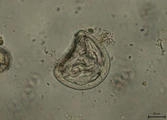

Picture Hint Answer % Correct

Cestode Anoplocephala

100%

Protozoaire Cryptosporidium

Cestode Dipylidium caninum

Protozoaire Giardia

Protozoaire Isospora ou Eimeria

Cestode Moniezia

Protozoaire Sarcocystis

Cestode Taenia

Protozoaire Toxoplasma